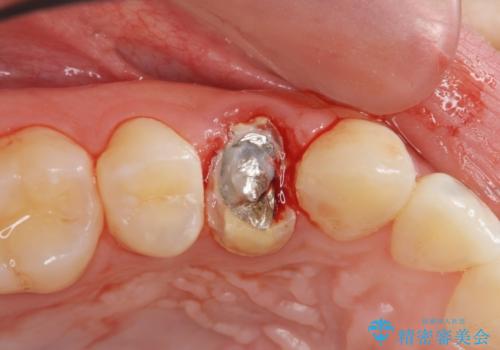

- 食事中に急に歯が折れ、周囲の歯も痛みだし治療を希望され来院されました。

ジルコニアクラウンによる咬合機能回復、根管治療を行い歯の痛みをとり長期的な予後の見込める治療を計画します。

- 26万円(仮歯・ファイバーコア・ジルコニアクラウン×2)費用は治療当時の料金となります